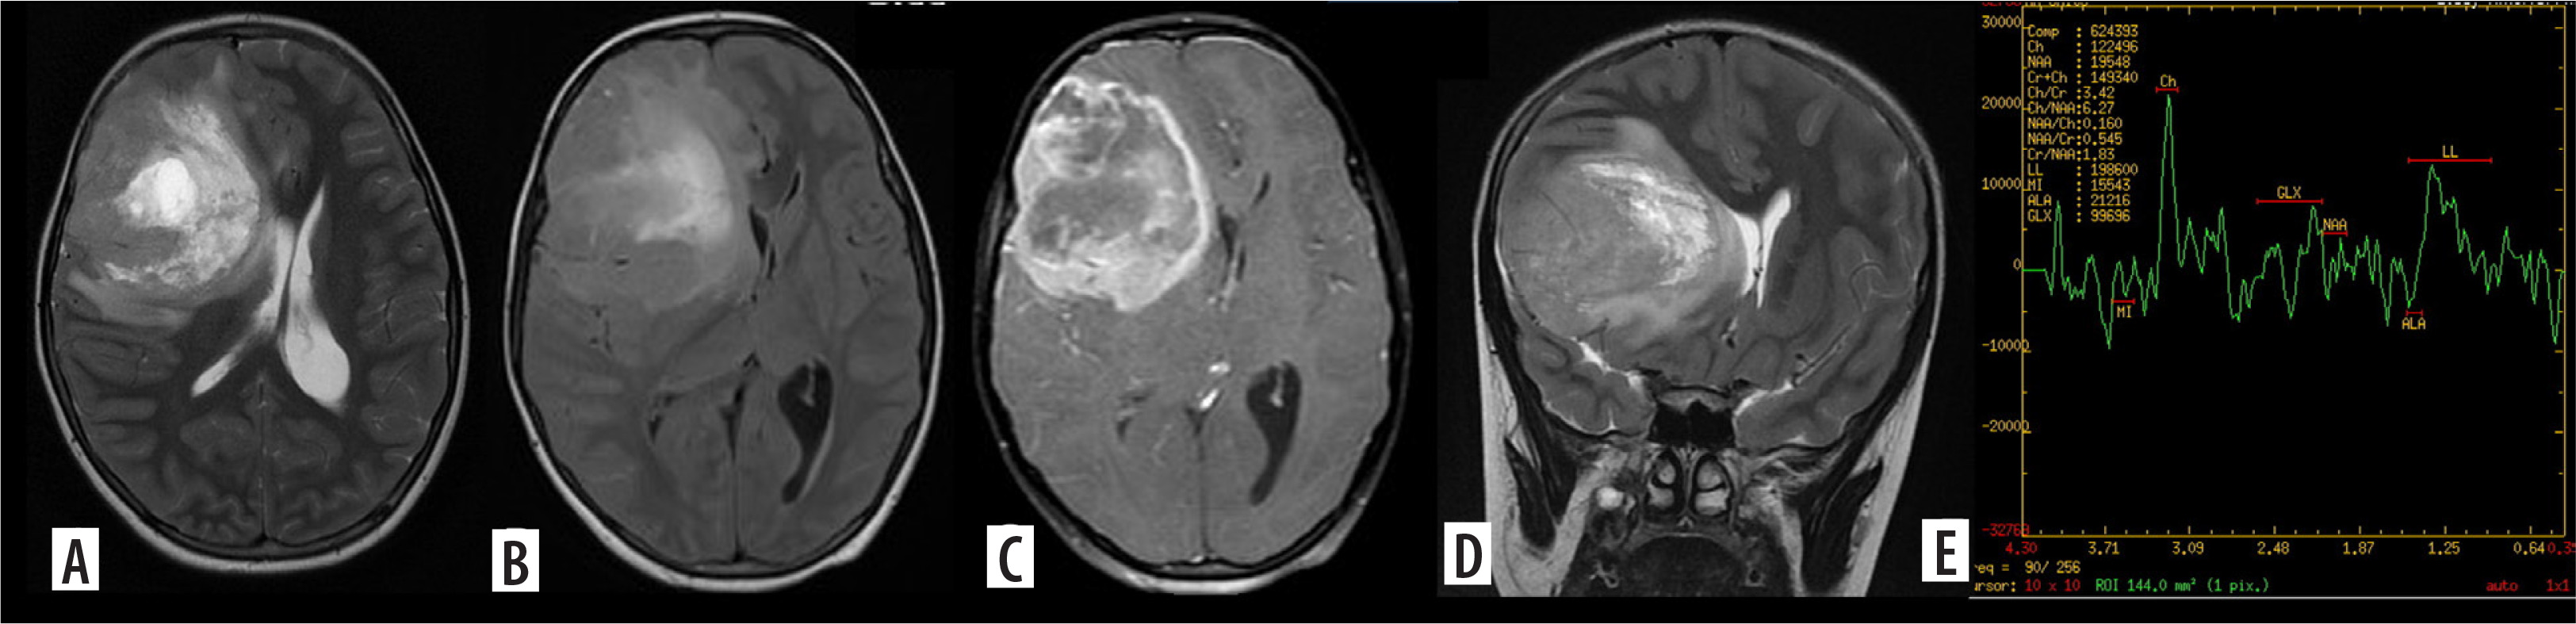

Figure 4

Multifocal glioblastoma. Axial and coronal T2 images (A, B), shows a diffusely infiltrative T2 heterogenous tumour, with heterogenous enhancement (C) in the right parieto-temporal lobe and the thalamus showing necrosis, haemorrhage and extensive surrounding non enhancing oedema. There is subependymal involvement and mild hydrocephalus, likely due to partial obstruction of the right foramen of Monro. Another discrete lesion is seen in the corpus callosum anteriorly